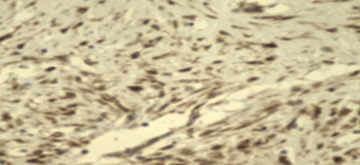

Inmunohistoquimica: CD34 y CD 17 negativos. Betacatemina positivo (figura 3).

La ausencia de expresión CD34 y S100, betacatenina positivo apoyan la naturaleza fibromatosa de la lesión7.